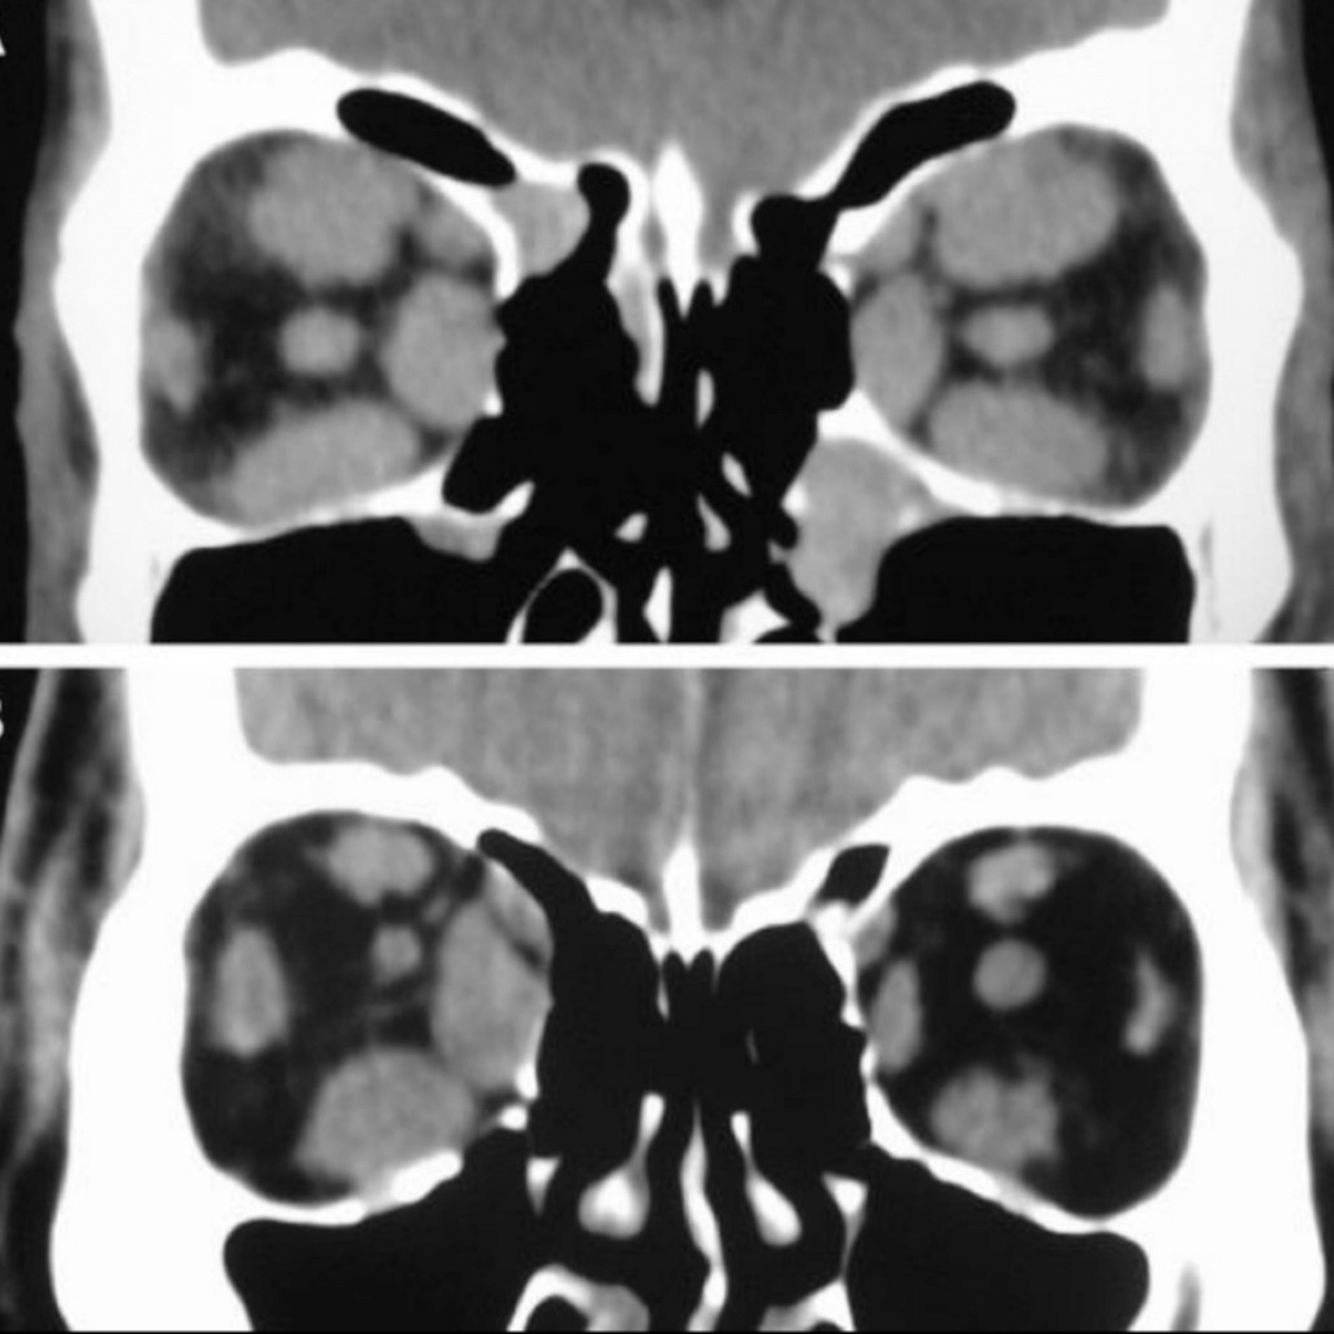

Retinoblastoma subtipos:

A

• Bilateral

.

• Trilateral: + t. pineal

• Cuadrilateral: bilateral + t. pineales + t. supraselares

Q

Clínica de RB:

• Leucocoria

• Pérdida de visión, estrabismo

• Niños menores de 4 años

¿Qué se aprecia en RB por USG?

Lesión hiperecogénica con calcificaciones

Hallazgos de TC de RB:

• Calcificación manchada o punteada

• Masa con densidad intermedia

• Capta contraste